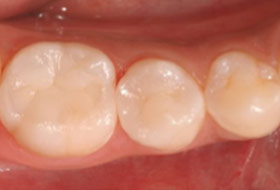

銀⻭を⽩くする治療としては「セラミック治療」が有名ですが、最近ではダイレクトボンディング法という治療法も広まってきています。

ダイレクトボンディング法はセラミック治療より費⽤が安く、 また短い期間(最短1⽇)で治療できるのがメリットです。 また従来の詰め物や被せ物を利⽤した治療法よりも、⻭を削る量を少なくできます。

さらにダイレクトボンディング法は「⻭の表⾯の傷や⽩濁の改善」や「すきっ⻭の改善」、「⻭の形の改善」などにも応⽤できます。 適応症例が限定されますが、ご興味のある⽅はぜひ当院までお問い合わせ下さい。

ダイレクトボンディング法による治療。時間の経過とともに変色する可能性があります。